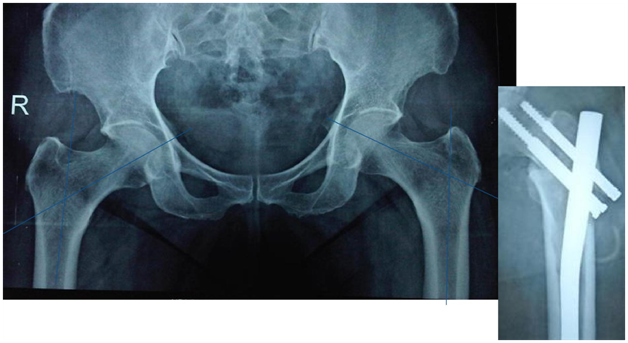

Indications (Figure 1)

1. Unstable IT fractures

1. Comminuted

2. Reverse oblique

3. Subtrochanteric extension

2. Associated shaft fracture

Figure 1 PFN in IT fractures.